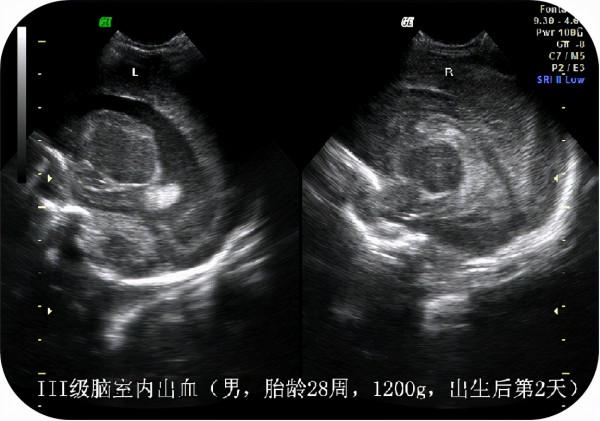

1.新生兒顱內出血;

顱內出血是指血管破裂從而引起出血,進而會造成腦缺氧。

在新生兒群體當中,發生顱內出血的機率十分高,因為新生兒的腦部發育不成熟,腦部血管管壁較薄,血管很容易破裂,懷孕期間出現妊娠期糖尿病或高血壓的產婦生下來的新生兒出現顱內出血的機率更大。